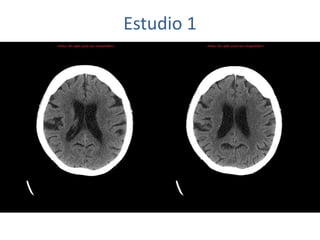

Estudio 1